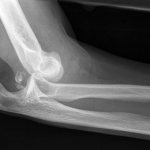

Травма на рентгене.

- Рентгенографическое обследование. Снимки производятся в двух проекциях.

Для диагностики врачам обычно хватает клинических симптомов, осмотра пациента. С целью подтверждения диагноза больному делают рентгенографию локтевого сустава в двух проекциях. Исследование позволяет визуализировать смещение, выявить сопутствующие переломы. Рентгенографию выполняют до вправления и после него.